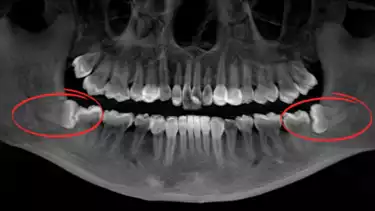

Kondisi ini juga pernah dialami oleh Aurel Hermansyah, penyanyi sekaligus aktris terkenal di Indonesia. Saat melihat hasil rontgen gigi Aurel yang lama, drg. Devya mengingat kembali kondisi serius yang pernah dialami Aurel akibat posisi gigi bungsunya yang "tidur". Gigi tersebut tidak hanya menekan gigi depannya tetapi juga menimbulkan rasa sakit yang intens.

“Ini kan dia sudah mendorong, sudah mepet banget sama gigi depannya. Harusnya posisinya lurus ke atas, seperti gigi yang di sebelahnya. Kalau seperti ini, kotoran bisa masuk ke sela-selanya, dan menambah sakit,” jelas drg. Devya.

Aurel mengingat kembali saat rasa sakit itu terjadi. “Makanya dulu suka sakit ya, Dok? Ingat ngga?” tanyanya, mengenang rasa sakit yang dirasakannya. Rasa sakit itu terutama disebabkan oleh posisi gigi bungsu yang menekan gigi di depannya. Selain itu, adanya kemungkinan sisa makanan yang terperangkap di sela-sela gigi dan gusi juga dapat memperburuk kondisi, menambah risiko iritasi atau infeksi.